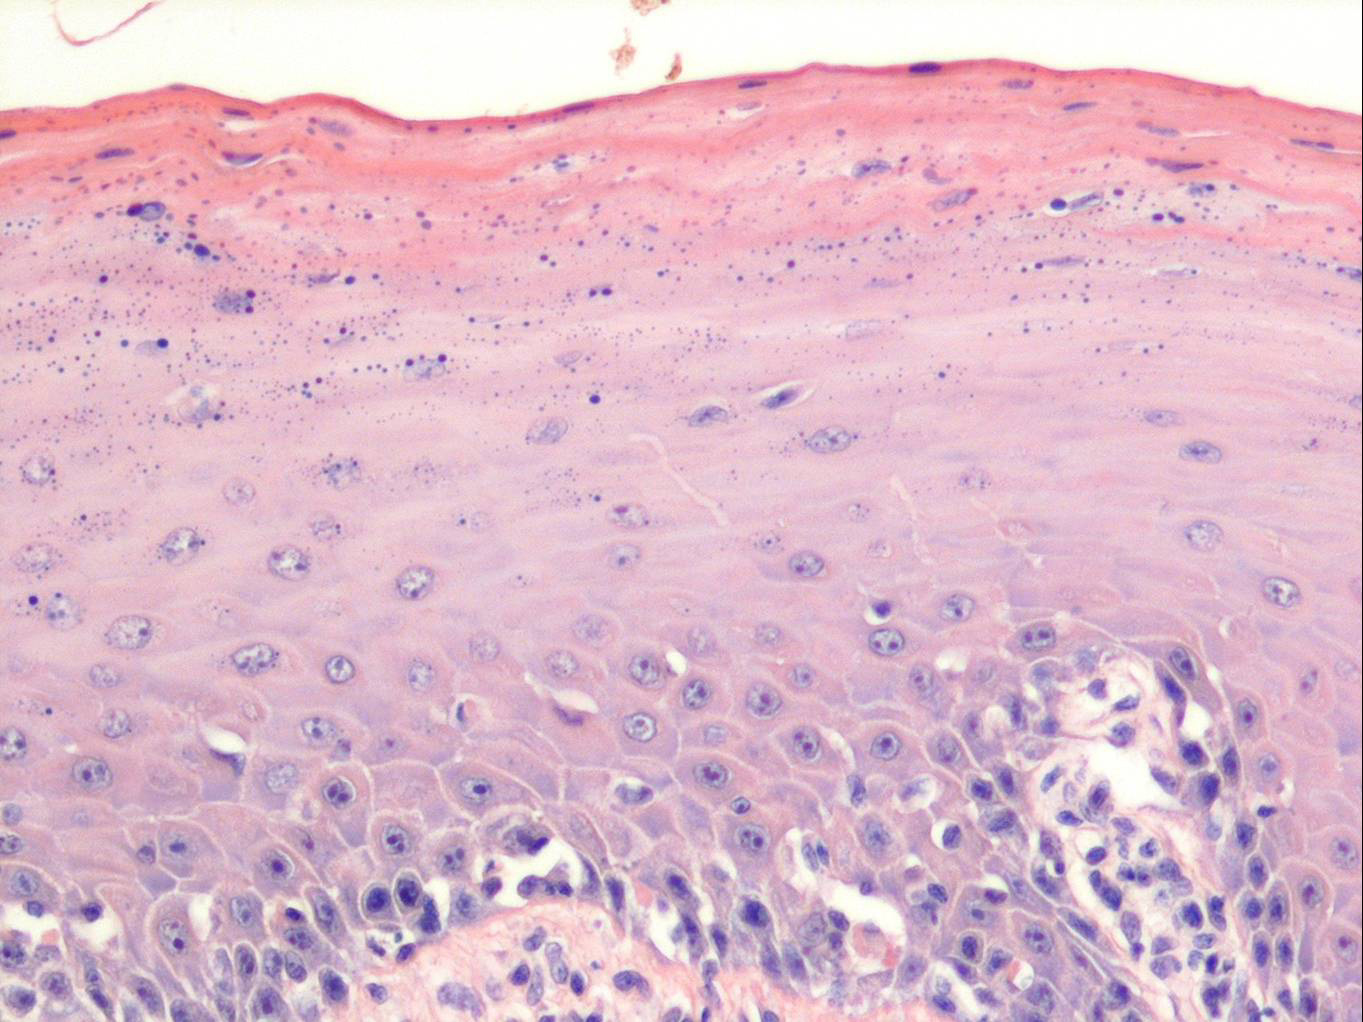

Oropharyngeal lichen planus = الحزاز المنبسط الفموي البلعومي